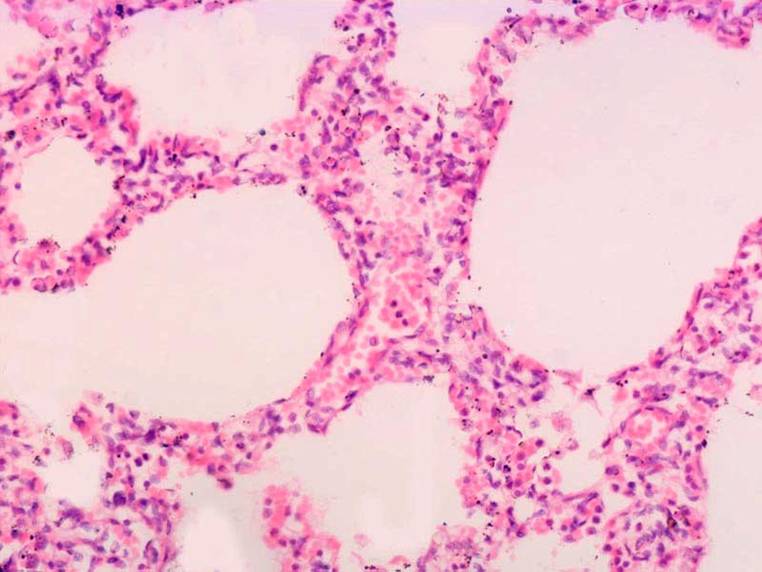

病理显示,肺大体标本呈暗红色,重量增加,外观饱满,质实变硬,触压不萎陷。肺切面为暗红色斑点与灰白色相间,并有交错分布的灰白纤维组织条索和小灶性瘢痕组织。光镜检查:早(渗出)期病变(肺损伤后约1周内)时,肺泡间隔因血管扩张、基质水肿和炎性细胞浸润而弥漫增厚,其中以淋巴细胞浸润为主,亦有浆细胞、单核(或巨噬)、中性和嗜酸粒细胞及少许成纤维细胞;肺泡上皮增生和化生形成柱状,加宽了肺泡间隔;肺泡腔内侧正常或有少许蛋白性物质及细胞渗出。此时的肺泡间隔相对较薄、肺泡结构尚正常,对治疗反应良好。随着病情的进展,血管内皮及肺泡上皮细胞受损、坏死和脱落;肺泡腔内形成均匀粉染的嗜酸性物质——透明膜。约2周时,DAD进入晚(增殖或机化)期,肺泡间隔出现广泛增生的成纤维细胞和肌纤维细胞,而胶原沉积却较少,这使得肺泡间隔明显增宽;毛细血管被纤维组织替代而数量减少;肺小动脉内膜增生、管壁增厚,有时在中小肺动脉内可见机化的栓子;肺泡因纤维化和闭锁而减少,残存的肺泡形状不规则、大小不一,或呈裂隙状或异常扩张。由于Ⅰ型肺泡上皮细胞的坏死,Ⅱ型上皮细胞增生、呈柱状或鞋钉样排列,衬于肺泡表面;这与UIP中有相当数量的细支气管上皮细胞参与分布于肺泡表面的情况有所不同。另外,呼吸性细支气管上皮可出现鳞状化生。数周后,蜂窝肺即可出现。

电镜检查:Ⅰ型肺泡上皮细胞丧失,局部乃至大面积的肺泡上皮细胞基底膜剥脱,Ⅱ型肺泡上皮细胞及毛细血管内皮细胞的胞浆水肿和坏死脱落。细胞碎片与纤维蛋白、红细胞及表面活性类物质的混合物沿肺泡表面分布,这尤其见于镜下的透明膜形成区。散在的炎性细胞,尤其是巨噬、淋巴和浆细胞存在于肺泡腔中;而间质中水肿的基质及不同数量的胶原和弹性纤维周围分布着大量成纤维细胞、少量炎症细胞及散在的原始实质细胞。进一步的研究发现,间质中大量成纤维细胞及少量胶原的存在并不是造成间质增厚的惟一原因。由于肺泡上皮细胞基底层的剥脱,使得大部分肺泡均有不同程度的塌陷。此种塌陷的另一特征是塌陷的肺泡部分中,有许多邻近的上皮细胞基底层相互重叠和对折。这种由二层基底层组成的结构以匍行的方式插入肺泡壁,在间隔内部形成深的裂隙。当Ⅱ型肺泡上皮细胞沿剥脱的基底层重新上皮化时,细胞并不深入裂隙之间,而是沿裂隙的两个外侧面覆盖。而若肺泡全部塌陷时,相互分离的肺泡间隔此时也会发生对折。Ⅱ型肺泡上皮细胞重新生长时,它并不是全部直接生长在脱落的基底层表面,有部分的上皮细胞与基底层之间存在有一层残留的炎症初期时的肺泡腔内渗出物。这两种现象的结果是,当Ⅱ型肺泡上皮细胞增殖重新覆盖脱落的上皮基底层时,细胞所覆盖的是塌陷部分,而不是沿完整的基底层重新呈线样排布和重新扩张肺泡;由于一层部分重叠的肺泡壁结合进了单一增厚的肺泡间隔,再加上部分区域肺泡腔内渗出物的“渗入间隔”,这就与其他因素一起造成了镜下所见的间质纤维化。